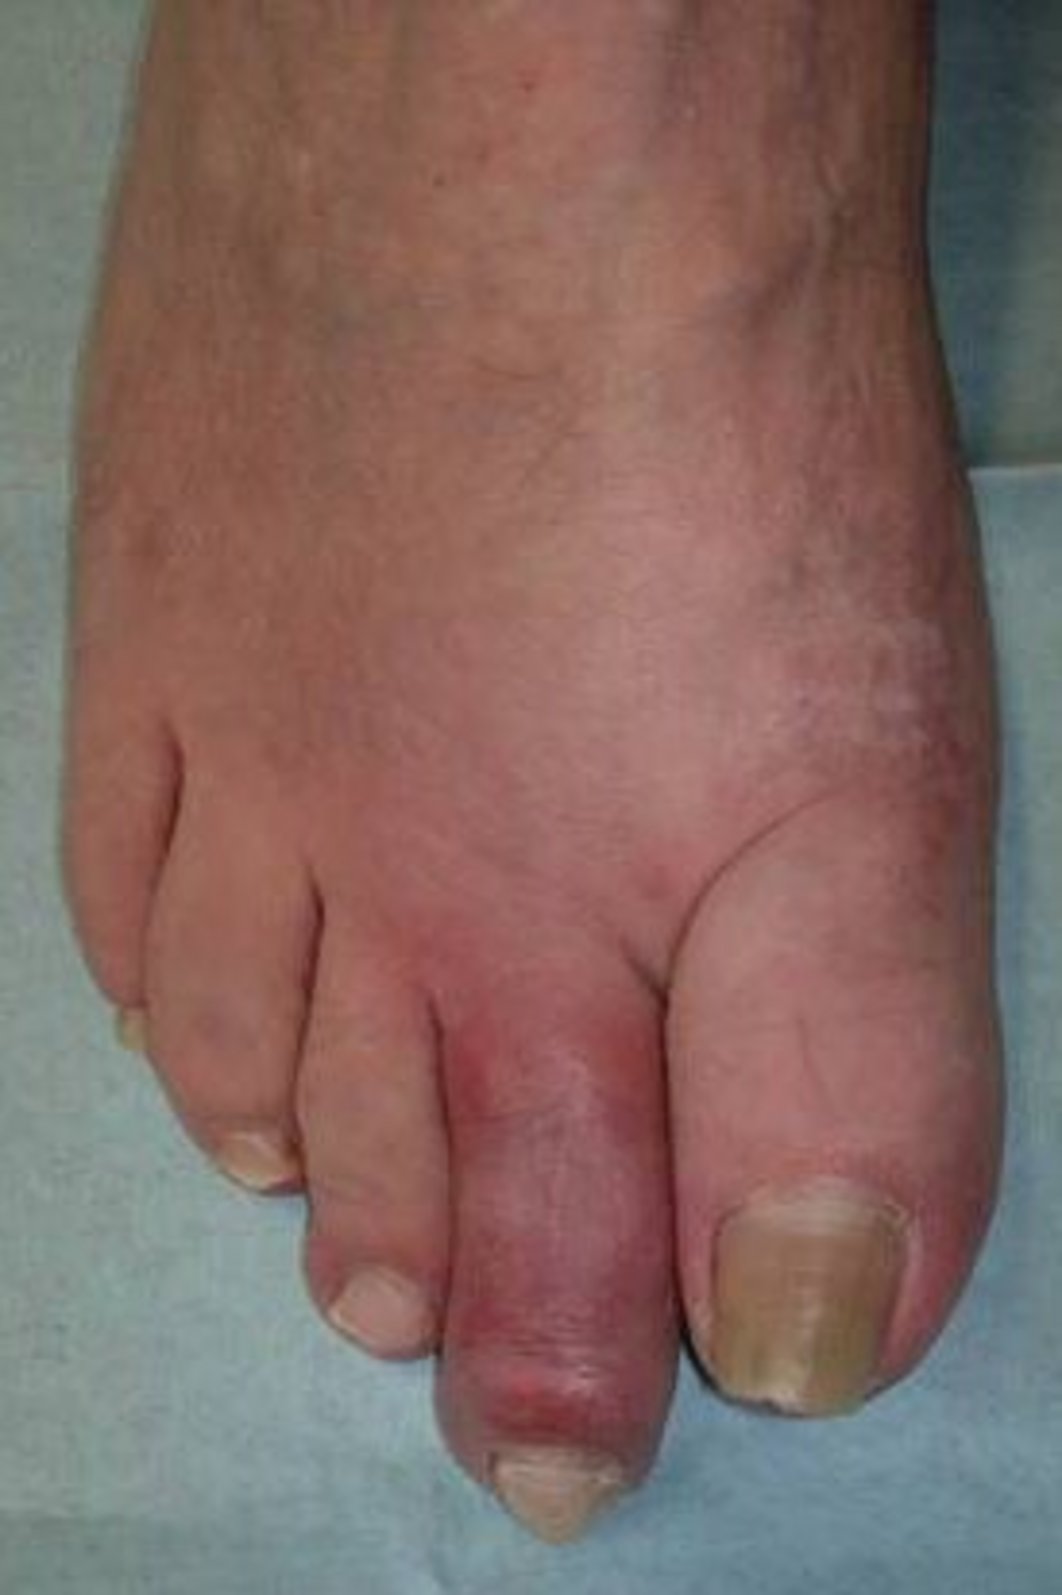

Arthritis Urica Definition. by mayo clinic staff. It's characterized by sudden, severe attacks of pain, swelling, redness. gout is a common and complex form of arthritis that can affect anyone. high uric acid levels can increase the risk of gout, which is a type of arthritis, and lead to other health problems. gout is a type of inflammatory arthritis that causes sudden, painful attacks of swelling, tenderness, and redness in one or more joints. low uric acid is defined as less than 2 mg/dl. A high uric acid level can be the result of the body making too much uric acid, not getting rid. Learn more about uric acid here. You’ve probably heard about high uric acid, or hyperuricemia,. gout is a type of arthritis that happens when you have too much uric acid in your blood and it forms sharp crystals. gout is a type of inflammatory arthritis caused by small crystals of a chemical called uric acid that form in the joints. gout is a type of arthritis caused by an excess of a chemical called uric acid, also called urate.

Arthritis Urica Definition by mayo clinic staff. gout is a type of inflammatory arthritis that causes sudden, painful attacks of swelling, tenderness, and redness in one or more joints. low uric acid is defined as less than 2 mg/dl. gout is a type of inflammatory arthritis caused by small crystals of a chemical called uric acid that form in the joints. high uric acid levels can increase the risk of gout, which is a type of arthritis, and lead to other health problems. gout is a common and complex form of arthritis that can affect anyone. A high uric acid level can be the result of the body making too much uric acid, not getting rid. You’ve probably heard about high uric acid, or hyperuricemia,. by mayo clinic staff. Learn more about uric acid here. It's characterized by sudden, severe attacks of pain, swelling, redness. gout is a type of arthritis caused by an excess of a chemical called uric acid, also called urate. gout is a type of arthritis that happens when you have too much uric acid in your blood and it forms sharp crystals.